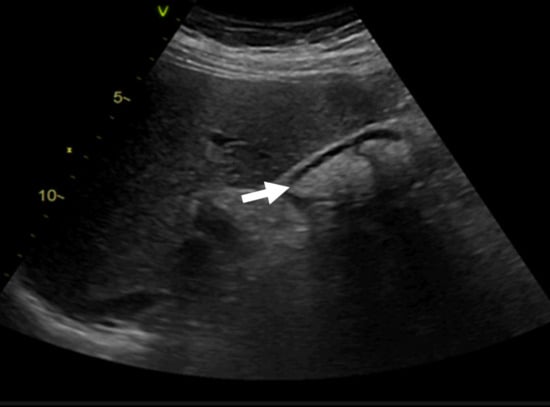

The antibiotic regimen was changed to linezolid (600 mg BID), ceftriaxone (2 g OD), and doxycycline (100 mg BID). Minimal clinical improvement occurred, but the following significant side effects of antibiotic therapy occurred: bone marrow aplasia resulting in pancytopenia due to linezolid and mildly symptomatic biliary sludge after ceftriaxone treatment (Figure 5).

Figure 5. Abdominal ultrasound showing biliary sludge (arrow) associated with ceftriaxone therapy.